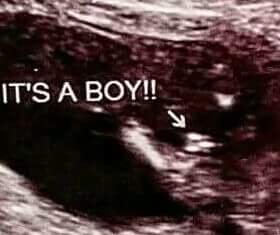

I got to talking with the L&D nurse, I showed her the elective ultrasound I got at 14 weeks and they told me boy..... She told me, not to buy blue because it looks like there is three lines.

what do you think, boy or girl?

I'm guessing boy. Those look like a "turtle"- triangular three lines, which would mean boy. Girls have three lines in a row, or close to it, which look like a hamburger sandwich.

The last pic is more ambiguous. The first one is very much a boy!